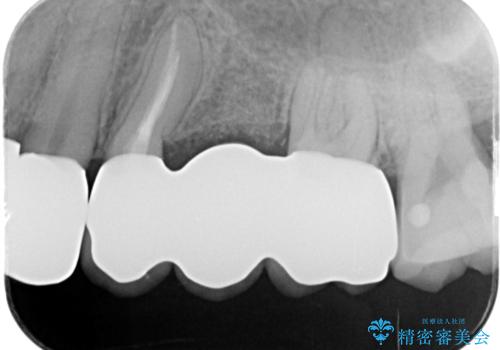

- 右上に装着されたブリッジのぐらつき、放置してしまった虫歯の治療を希望され来院されました。

ブリッジの支台、奥歯は虫歯や過大な咬合力により歯の破折・保存のできない大きな虫歯が認められます。

保存の難しい歯の抜去を行ったのち、咬合力にしっかりと耐えうる補綴設計としてブリッジや入れ歯ではなくインプラント治療を計画します。

噛む力の強い方は、ブリッジやクラウンが破損するだけでなく支える歯が割れてしまったりすることがよくあります。